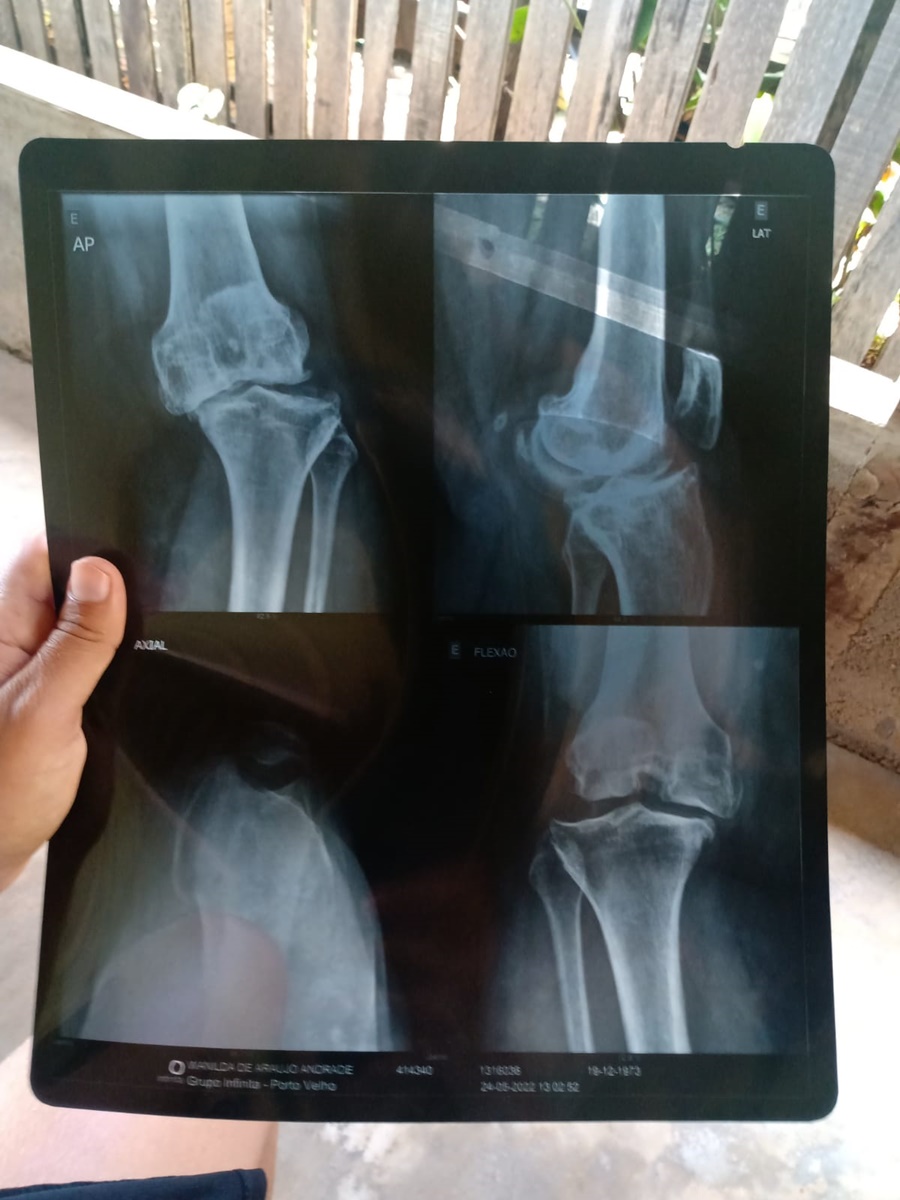

O drama vivido por uma moradora da capital há dois anos, ainda não tem data para acabar. Ela aguarda por uma prótese no joelho que, se não for feita, pode causar ainda mais danos à saúde da dona Wanilda de Araújo Andrade.

Na novela das filas das cirurgias eletivas do SUS, ela é mais uma personagem que espera para fazer a operação ortopédica no joelho esquerdo. Já são dois anos que ela luta por esse procedimento e, segundo ela, a situação está piorando e o médico que a acompanha já disse que, se demorar mais, Wanilda pode acabar ficando com o quadril comprometido.

A dona de cada de 49 anos tem dificuldade para fazer até mesmo as atividades mais comuns do dia a dia. Com dores constantes ela conta que tem recorrido a remédios e a injeções, que ajudam, mas, não resolvem o problema.